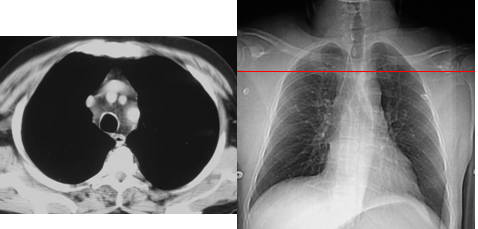

Normal anatomy:

CT/CXR correlation